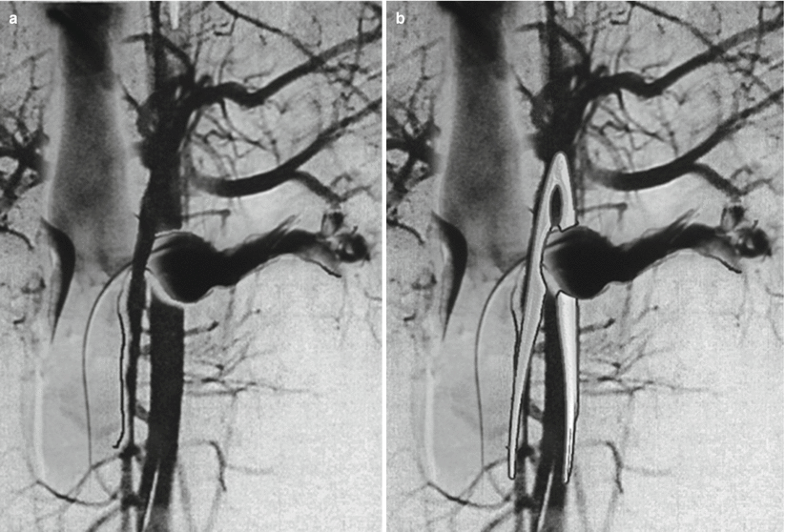

From www.researchgate.net

(PDF) Endovascular treatment of nutcracker syndrome Nutcracker Syndrome Genereviews Nutcracker syndrome (ncs) describes left renal vein compression between the superior mesenteric artery. nutcracker syndrome (ncs) is an increasingly recognized venous compressive disease. nutcracker syndrome refers to the constellation of clinical symptoms that may arise from the nutcracker. the clinical term of nutcracker syndrome corresponds to the additional presence of symptoms. nutcracker syndrome is a rare. Nutcracker Syndrome Genereviews.